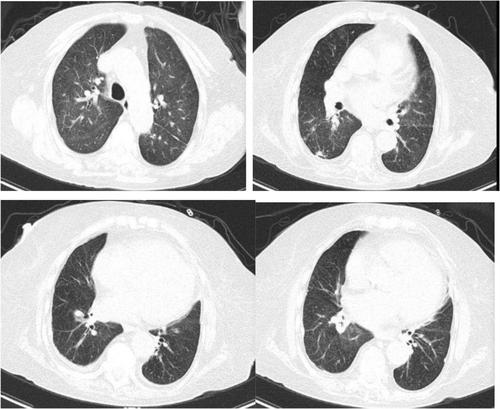

Allergic bronchopulmonary aspergillosis (ABPA) is an allergic lung disease caused by sensitivity to Aspergillus fumigatus. Diffuse lung lesions as a radiological presentation of ABPA are exceedingly rare, with no documented case in the literature. We present a case with asthma. High-resolution computed tomography (HRCT) of the chest revealed diffuse lung lesions. Additionally, arterial blood gas analysis revealed life-threatening acute Type II respiratory failure. Initially, there was suspicion of a mycobacterial infection. However, a subsequent diagnosis revealed the atypical presentation of ABPA. Finally, the patient's symptoms improved, and lung shadows were absorbed after undergoing mechanical ventilation with tracheal intubation and receiving methylprednisolone treatment.